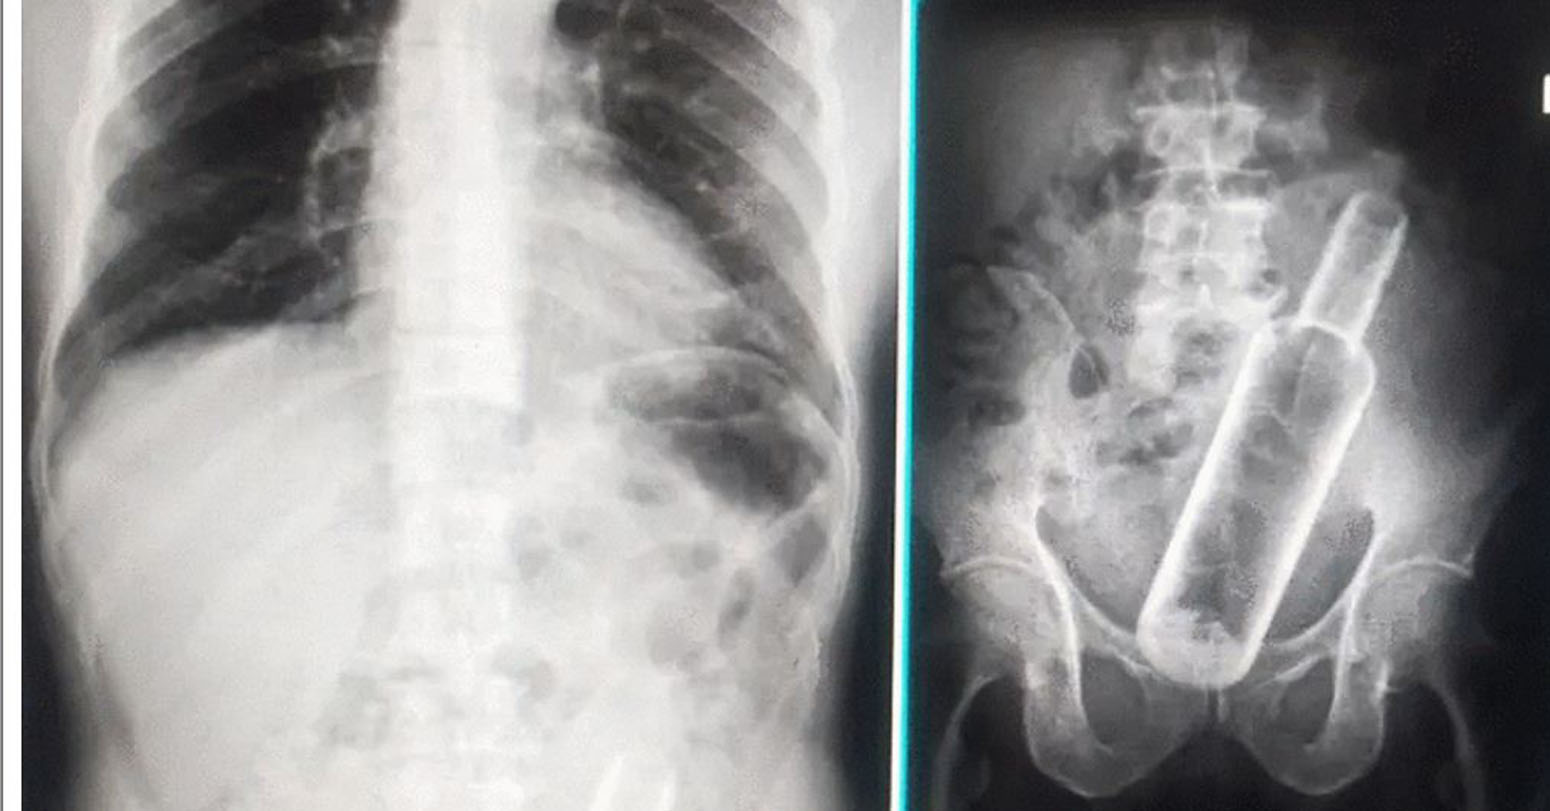

Doctors Find Vodka Bottle Inside an Elderly Man’s Stomach

Doctors have discovered an empty bottle inside the stomach of an elderly man. The incident took place in Dhangadhi. 61-year-old Jamansingh Rokamar reached Seti Provincial Hospital Dhangadhi for medical treatment, where doctors found the bottle inside his stomach. According to